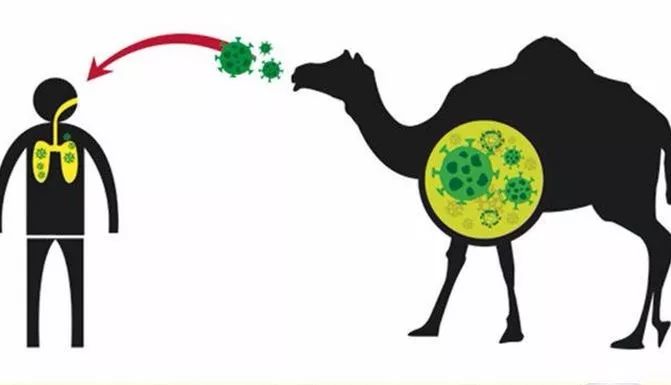

冠状病毒是人畜共患病毒,能在动物和人之间传播。例如,严重急性呼吸综合征(SARS-CoV)是从猫科动物传播给人类的,而中东呼吸综合征(MERS-CoV)是从单峰骆驼传播给人类的。现有证据表明,武汉新型冠状病毒2019-nCoV可能是人畜共患病毒。目前,几种已知的冠状病毒也在动物之间传播,而尚未感染人类。